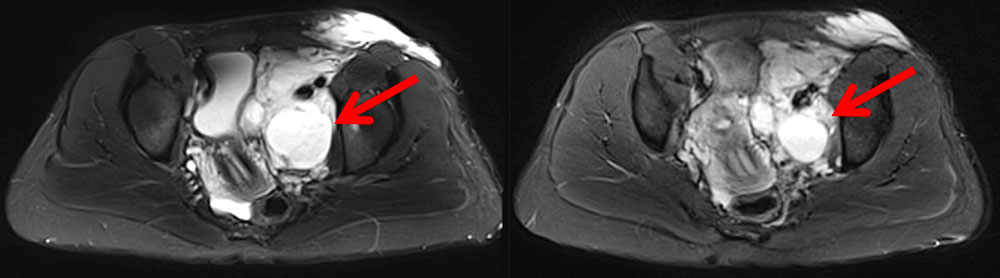

Positive reports of the use of sirolimus in individual case studies and smaller series of patients with extensive vascular malformations and corresponding severe clinical presentations have been published since 2011.

Sirolimus seems to be especially effective in the case of extensive, severe micro- or macrocystic lymphatic malformations.

A questionable effect or no effect in reducing bleeding frequency and proliferation activity in severe, complicated arteriovenous malformations has also been reported. The treatment outcome in fast-flow malformations appears to be significantly smaller and could not be demonstrated in all studies. The reason for this may lie in the genetic basis of arteriovenous malformations where dysregulation of another signaling pathway (RAS/MAPK/ERK signaling cascade) seems to be affected. By contrast, in slow-flow malformations upregulation of the PIK3CA/AKT signaling pathway is causative in the development of vascular anomalies. Sirolimus (rapamycin) is a central inhibitor of this mammalian target of rapamycin (mTOR) pathway, which may explain its effect.